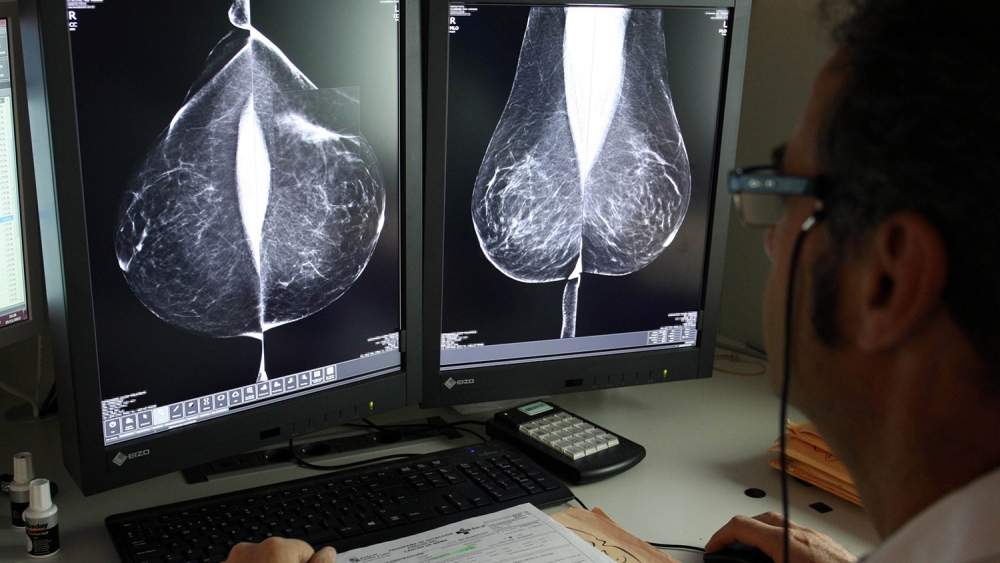

Diversos estudios científicos demuestran que la inteligencia artificial se ha convertido en un aliado de los radiólogos, con un alto rendimiento en los cribados, que pueden ayudar a evaluar, en el caso del cáncer de mama, las mamografías de bajo riesgo, como también en la detección temprana de esta enfermedad, siempre como una técnica de apoyo en la toma de decisiones. Incluso, algunos ensayos indican que la inteligencia artificial es capaz de predecir el riesgo de desarrollar cáncer de mama cinco años antes de que aparezca. En concreto estas conclusiones se extraen de un modelo desarrollado por el Instituto de Tecnología de Massachusetts, que se ha probado en varios países. No obstante, los expertos coinciden en la necesidad se seguir trabajando en más estudios y ensayos prospectivos.

También, coinciden en que ayuda a la lectura, lo agiliza y puede ayudar, también, ante la falta de radiólogos. En Castilla y León el programa de de detección precoz de cáncer de mama establece un sistema de doble lectura, que implica que pasen por manos de al menos dos radiólogos. El año pasado, la Junta optó por externalizar este servicio, práctica común en el conjunto del Sistema Nacional de Salud, con el fin de agilizar la lectura de 125.000 pruebas anuales y también después de que se ampliara el rango de edad hasta los 74 años de edad. Invirtió casi cuatro millones de euros, a los que podrían sumarse este año otros 3,3 millones, con un nuevo contrato.